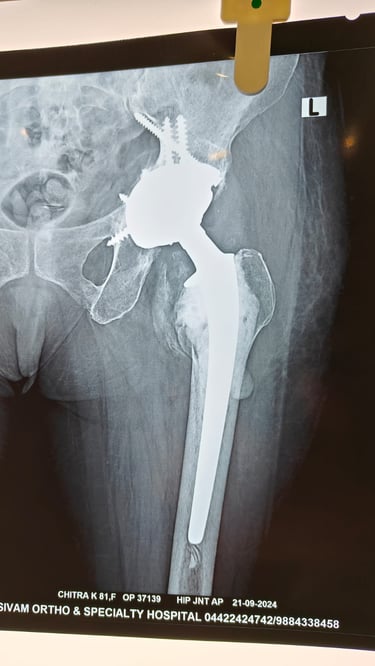

What is Hip Replacement?

Damaged hip joint is replaced with an artificial implant to improve function and reduce pain.

Diagnosis

X-ray

Total hip replacement